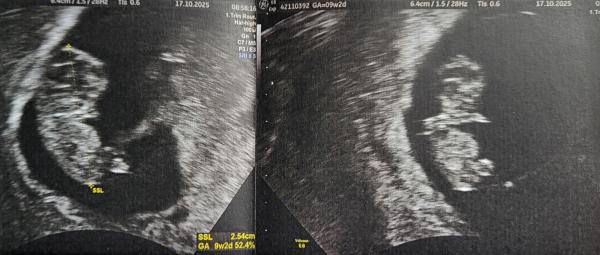

Hallo ihr Lieben. Wir möchten euch auch nochmal ein Update geben. Wir hatten heute an 9 plus 2 wieder einen US..Alles super zeitgerecht entwickelt und es hatte seine süßen kleinen Händchen am Mund und war sie am bewegen. Sieht aus wie ein Hamsterchen 🐹😍 (sieht man im Bild rechts, ist von oben dargestellt).. Der Ultraschall selbst war vaginal.. was meint ihr könnte es laut Ramzi sein? (Nabelschnur sieht man links im Bild und oben rechts dran dann die Plazenta) 😆😊 Wie geht es euch so? Wann ist euer nächster Termin? Unser erst in 4 Wochen aber dann denke auch das erste große Screening.. Lg und weiterhin alles Gute euch 🍀☺️🐞